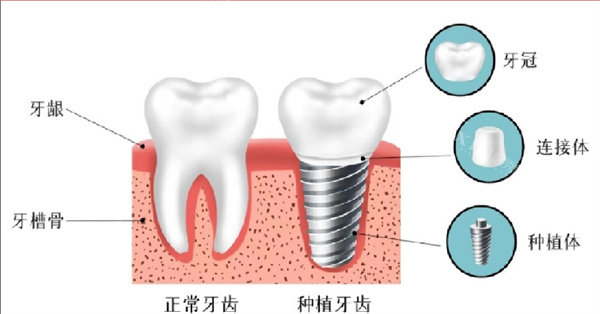

种植牙项目:

韩国登腾种植牙:3980元起/颗(含全瓷牙冠)

韩国奥齿泰种植牙:5980元起/颗(含全瓷牙冠)

瑞士士卓曼种植牙:12800元起/颗(含10年质保)

普通医生种植手术费:2000元/颗

院长级种植手术费:5000元/颗